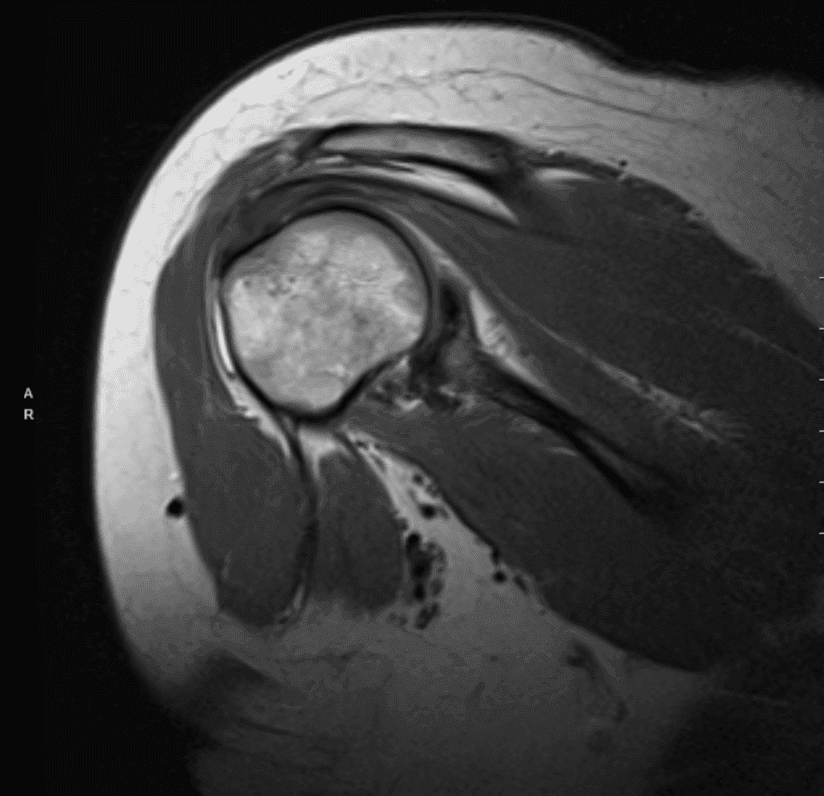

Realizó una resonancia magnética para el hombro derecho y mostró tendinosis difusa con una ruptura de grosor parcial de la huella de inserción anterior del tendón supraespinoso. Tendinosis difusa del infraespinoso con desgarro parcial intersticial. Tendinosis subescapularia.

Desgarro difuso del labrum superior/desgarro de SLAP. Desgarro del labrum posterior-inferior con desprendimiento parcial. Esguince capsular inferior frente a capsulitis adhesiva. Pequeño derrame. Quiste subcondral focal y defecto cartílago focal a lo largo del borde glenoideo posterior con patrón de desgaste subcondral temprano.

Bursitis subdeltoides subacromial. Cambio hipertrófico de la articulación AC con esguince capsular de grado I. Edema en la clavícula distal y el acrómio, que puede representar contusión o reacción al estrés. Estrechamiento del espacio subacromial. Edema de médula ósea con mayor tuberosidad compatible con la contusión ósea.

Resonancia magnética del hombro derecho